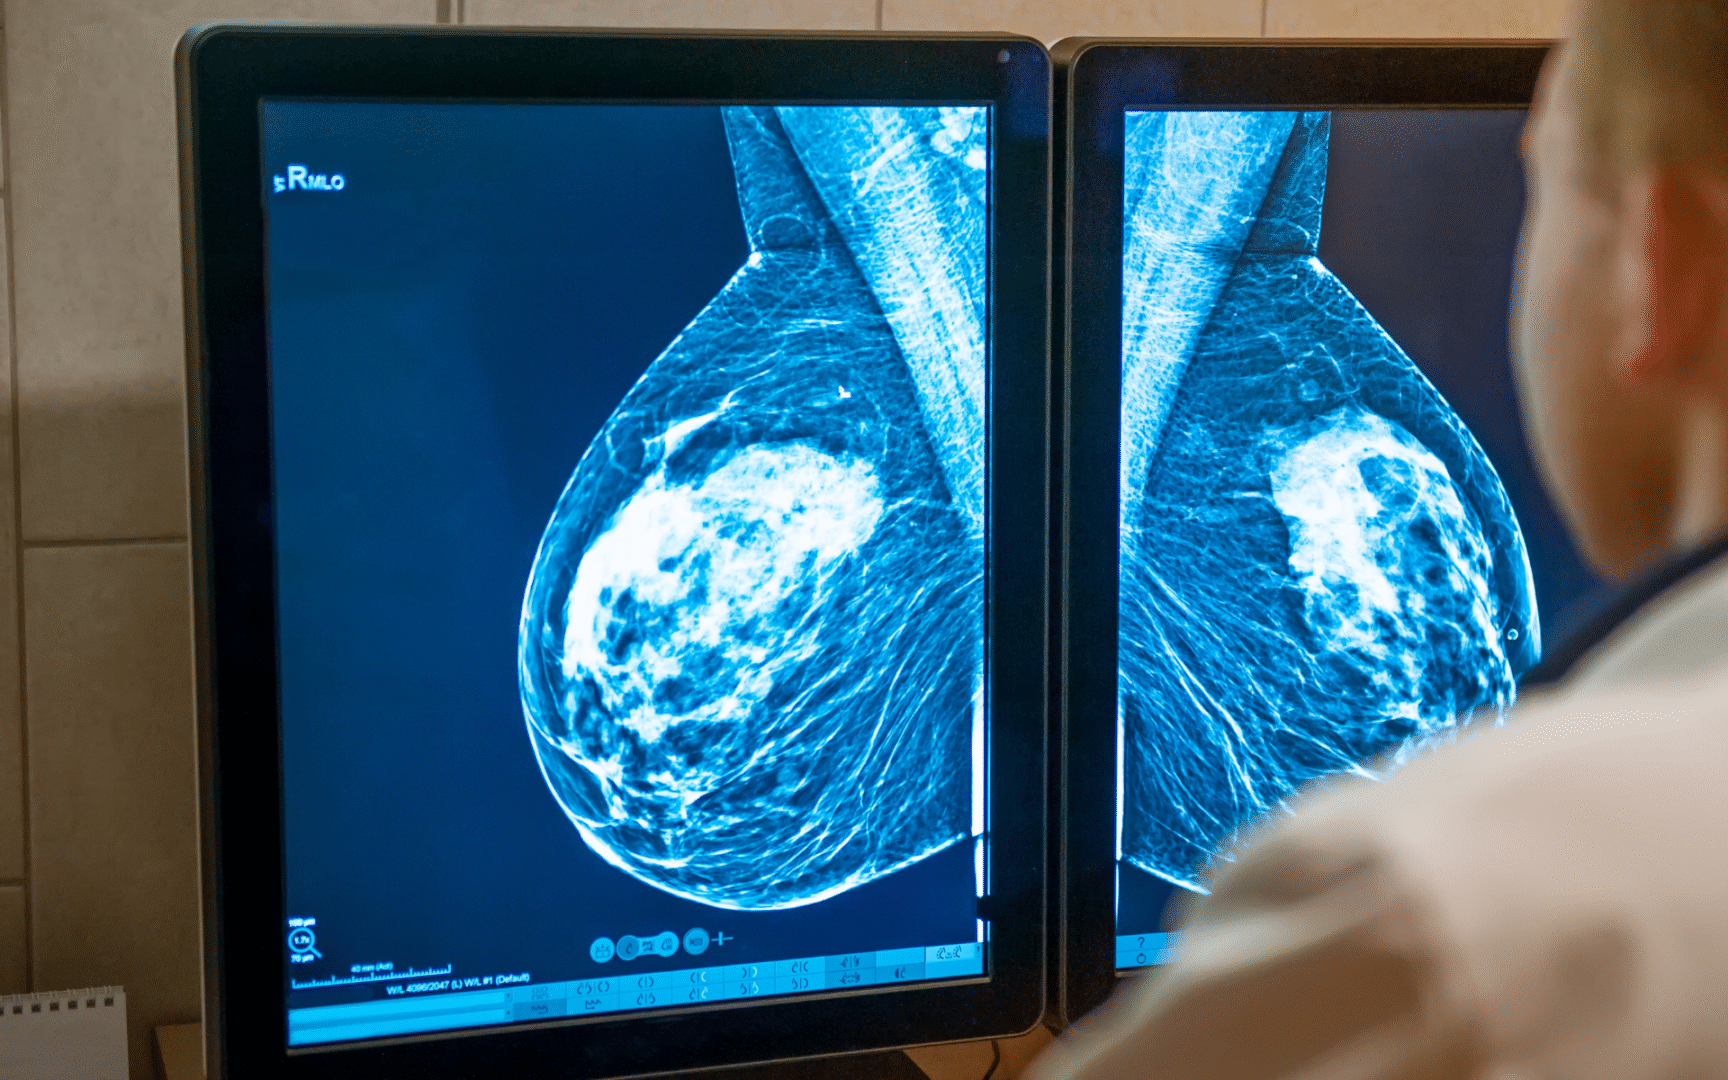

La mamografía es un examen médico que utiliza rayos X para obtener imágenes detalladas del tejido mamario. Su objetivo es detectar signos tempranos de cáncer de mama, incluso antes de que haya síntomas visibles o palpables.

- Se toman dos imágenes por cada seno: una de arriba hacia abajo y otra lateral.